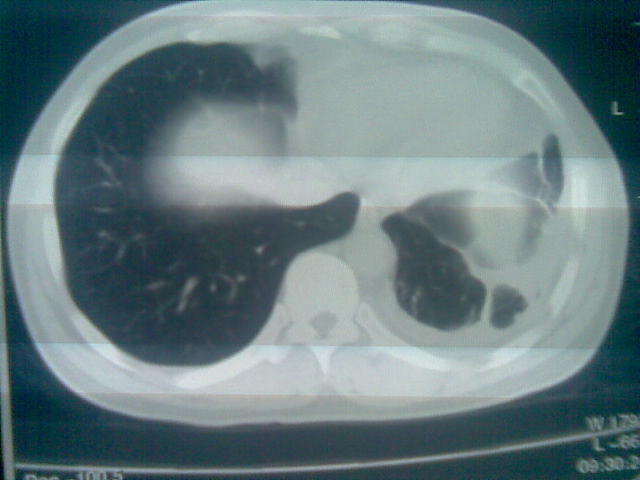

标题: CT23981:男,38岁阑尾炎术后透视胸腔积夜!做CT如下!积液包 [打印本页]

标题: CT23981:男,38岁阑尾炎术后透视胸腔积夜!做CT如下!积液包

.胸膜增厚粘连见少量气体。包裹脓气胸

左侧胸膜增厚、粘连+包裹液气胸。